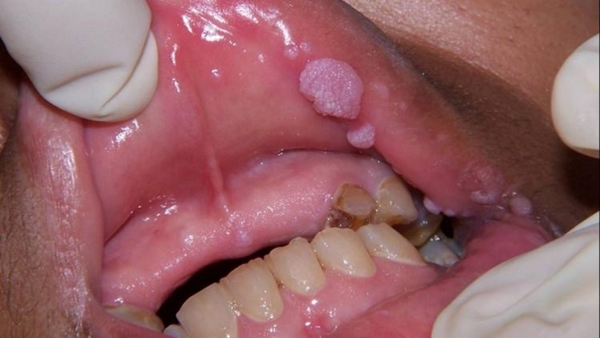

7- Ağız yaralarına iyi gelir.

8- Nasır ve siğillerin tedavisini hızlandırır.